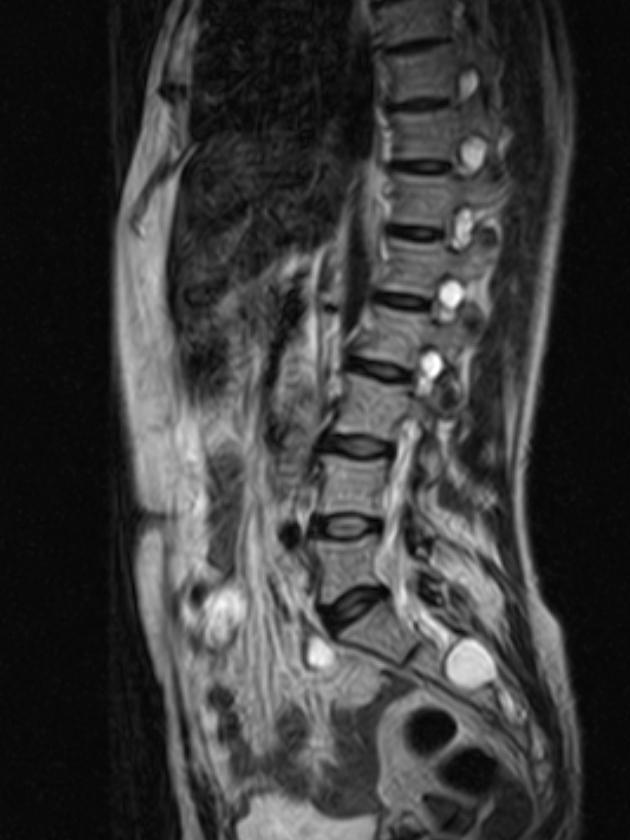

Family sources revealed a pivotal discovery to TMZ. Tests detected a rare cyst on Aaron’s spine. Physicians conducted additional exams to assess its nature. Questions lingered over whether the growth proved benign.[1]

This finding tied directly to the actor’s symptoms. The spinal anomaly potentially explained the leg paralysis. Medical teams weighed implications carefully. Aaron’s condition stabilized enough for these diagnostics. Supporters rallied through a GoFundMe campaign that raised over $38,000 for family support.[3]

Back surgery loomed as a possible next step. Such a procedure would demand extensive physical therapy afterward. Aaron might require a wheelchair temporarily. Experts anticipated a lengthy rehabilitation regardless of the cyst’s treatment.[1]